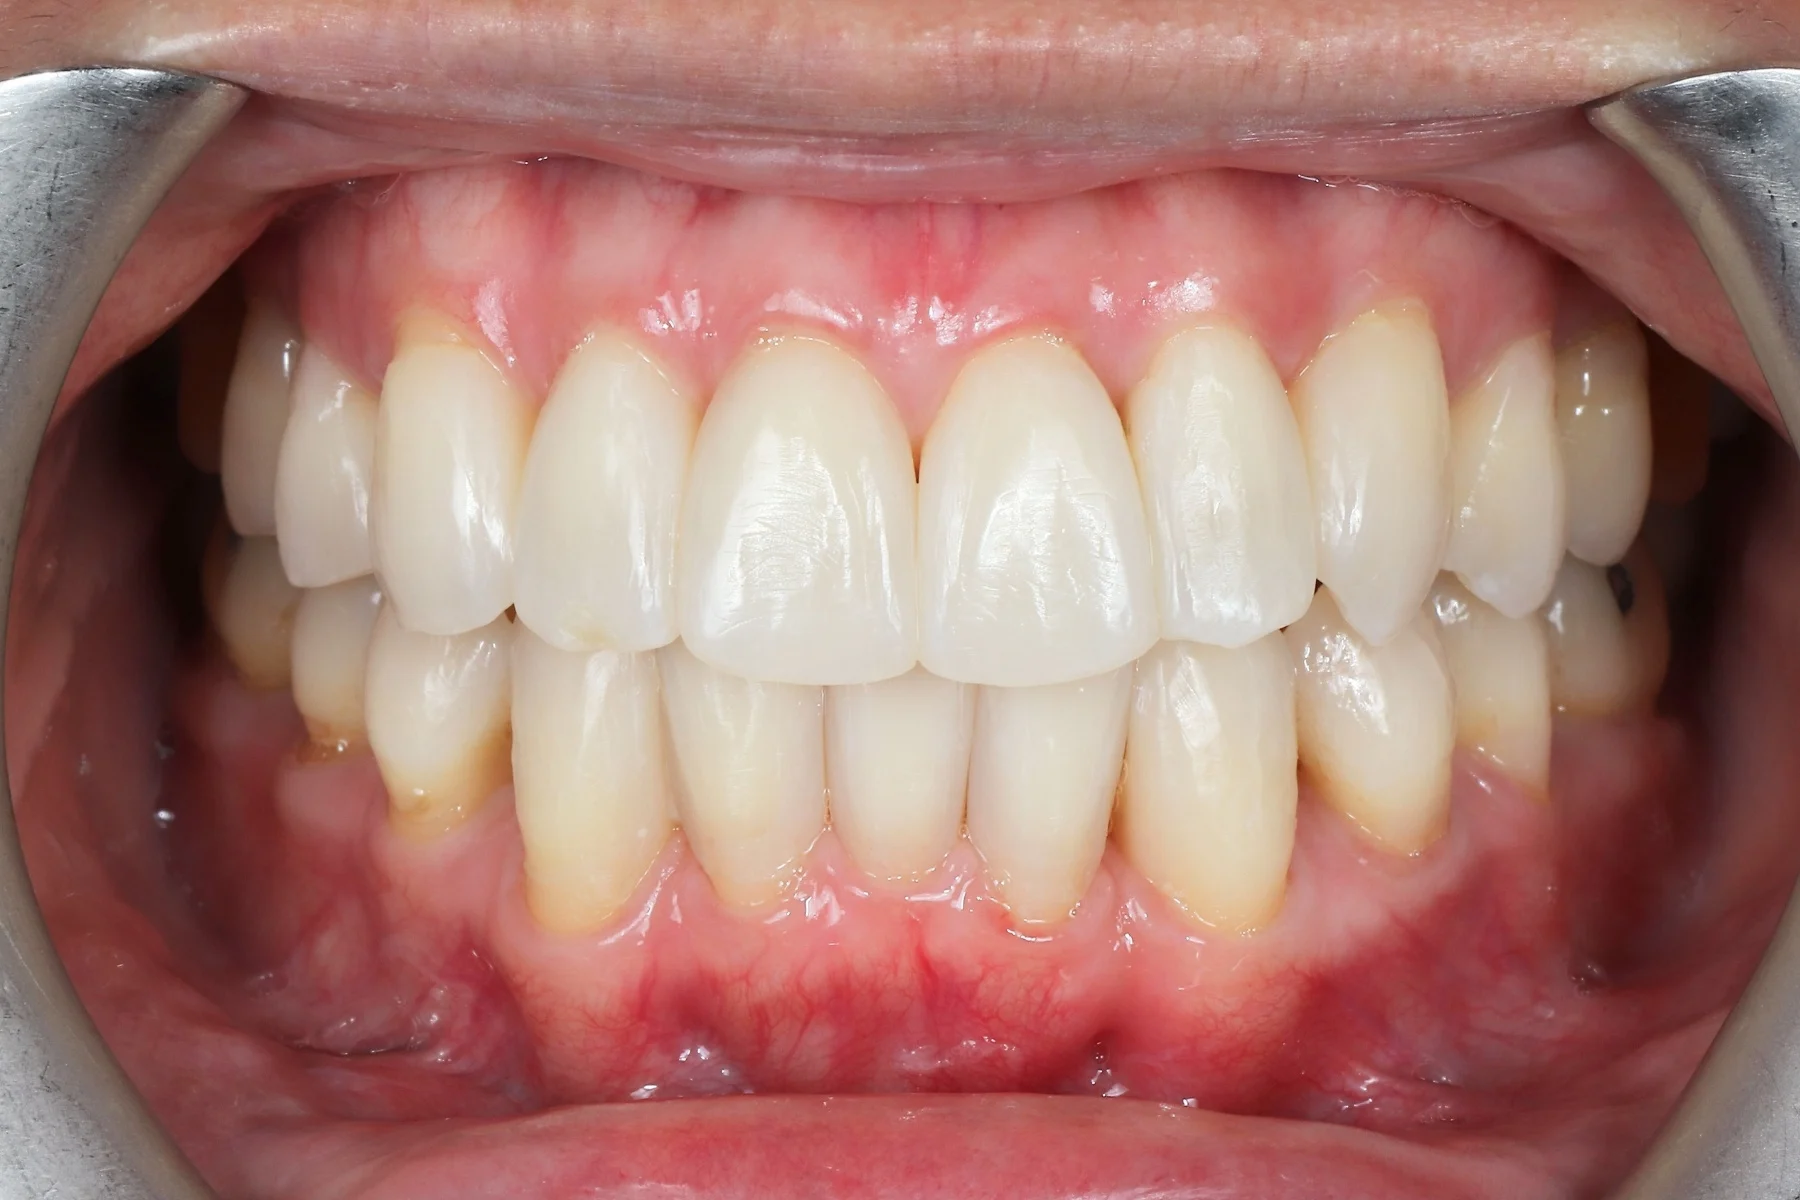

Dentist 陳昕 全口照護醫師 看診項目 前牙美學仿生樹脂補牙/全科牙醫 學經歷 臺北醫學大學牙醫系學士 前天主教新店耕莘醫院醫師 前臺北榮民總醫院醫師 亞洲齒列再生研究學會Advance植牙補綴專科訓練 微光私塾牙周雷射微創治療技術訓練 臺灣牙醫顯微美學治療學會會員醫師 中華審美牙醫學會會員醫師 CASE 案例分享 滲透型樹脂修復 主治醫師 陳昕 治療時間 單次療程 主訴 想處理前牙白白的色斑 前牙美學/仿生美學樹脂 主治醫師 陳昕 治療時間 單次療程 主訴 牙齒整齊,但門牙中間縫隙明顯,影響笑容美觀 前牙美學/陶瓷貼片 主治醫師 陳昕 治療時間 約1個月 主訴 兩顆門牙缺角,想要重建外觀 前牙美學/滲透型樹脂修復 主治醫師 陳昕 治療時間 單次療程 主訴 門牙有長期存在的白斑與表面不平整,影響外觀與自信 前牙美學/仿生美學樹脂 主治醫師 陳昕 治療時間 約兩週 主訴 矯正後的黑三角縫問題 前牙美學/仿生美學樹脂 主治醫師 陳昕 治療時間 約三週 主訴 因牙周病產生的黑三角縫 前牙美學/牙冠增長術、仿生全瓷牙冠 主治醫師 陳昕 治療時間 約6個月 主訴 牙齒排列不整、假牙外觀不自然 前牙美學/仿生美學樹脂 主治醫師 陳昕 治療時間 約兩週 主訴 露齒笑時黑三角縫明顯,覺得不好看 前牙美學/仿生美學樹脂+噴砂美白 主治醫師 陳昕 治療時間 約兩週 主訴 露齒笑時有不好看的黑三角縫,容易有茶垢沉澱,讓縫隙更明顯 牙齒美白/噴砂美白+冷光美白 主治醫師 陳昕 治療時間 單次療程 主訴 前牙泛黃且染色明顯,影響外觀與自信 牙齒美白/噴砂美白 主治醫師 陳昕 治療時間 單次療程 主訴 牙齒表面有喝咖啡、抽菸造成的外部染色,影響外觀與自信 點此載入更多 Column 精選文章 FEATURED 精選案例 【牙科修復案例】陶瓷貼片可以做一顆嗎?單顆門牙缺角修復,陶瓷貼片重建自然笑容 2026-01-16 從「假笑」到「自然笑容」的轉變——認識「牙冠增長術」與「仿生全瓷冠」 2025-10-14 Video 精選影音